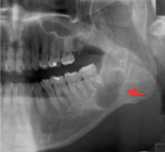

2、对颌牙齿伸长

大连齿科医院口腔专家指出长时间缺牙可导致相对的牙齿伸长,为以后修复造成不便,同时伸长的牙齿与相邻牙齿之间亦容易嵌塞。